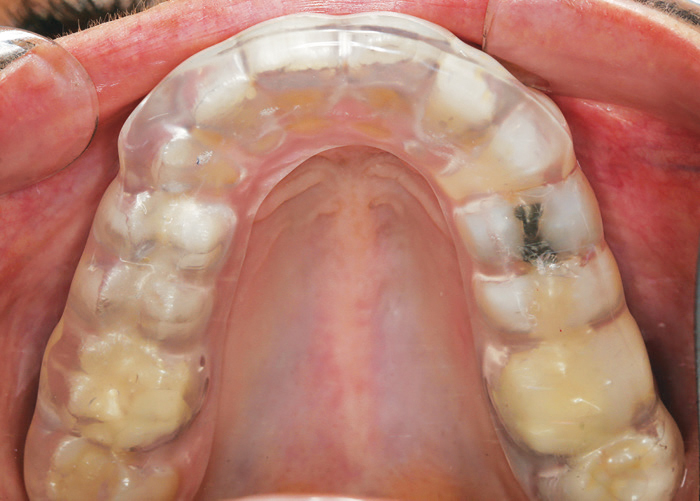

FIGURE 1B. Maxillary bite splint processed on the digital model.

FIGURE 1C. Maxillary bite splint fabricated from a fullarch scan.

As noted, the initial applications for chairside CAD/CAM systems were to produce single-tooth restorations, but now some offer the ability to fabricate short-span FPDs, adhesively bonded FPDs, and provisional restorations in the dental office. One of the more advantageous advances is the ease and efficiency with which full-arch scans can be recorded. This has led to improvements in managing more complex occlusal schemes and movements through virtual articulators that can simulate lateral and protrusive guidance. Full-arch scans can also be used in the fabrication of tooth-borne appliances, such as bite splints (Figure 1A to Figure 1C). It has also led to more orthodontic applications, especially in the area of clear aligner therapy.